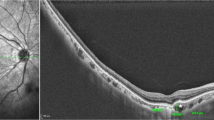

To describe and correlate the morphological and clinical features of focal choroidal excavation (FCE).

All 16 patients with FCE had unilateral involvement. The mean age of diagnosis was 52.56±14.00. The mean greatest linear dimension (GLD) of FCE was 636.25±265.11 μm. The mean choroidal thickness was 183.63±52.39 μm. Fourteen FCEs (87.5%) were conforming and two were non-conforming (12.5%). In the eyes with FCE, concurrent macular pathology was present in four cases (25.0%). Tractional pathologies of macular pucker and macular scar corresponded to the two non-conforming FCEs in the series. Polypoidal choroidal vasculopathy (PCV) and lacquer crack had a close topographic relationship with the FCE. The mean GLD was significantly larger in eyes with concurrent macular pathology than those without (878.00 vs 555.67 μm, P=0.029). In the fellow eyes, concurrent macular pathology was present in 5 cases (31.3%): PCV in 3 cases and chronic central serous chorioretinopathy in 2 cases.

As a significant proportion of FCE is associated with concurrent macular pathology in the involved or fellow eye, angiography for both eyes is recommended even for asymptomatic cases. The GLD of FCE may have clinical value in risk stratification.